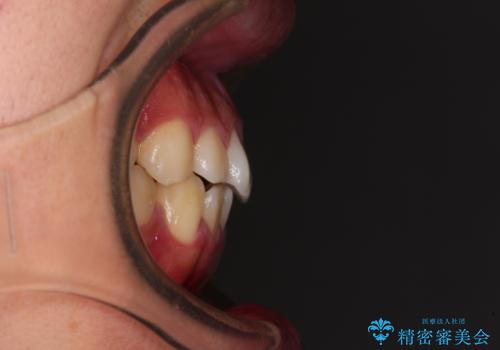

- 上下前歯の叢生を気にして来院された患者様です。

費用を抑え、期間もあまりかけずに治療をしたいとのことで、インビザライン・ライトを用いて矯正治療を行うこととしました。